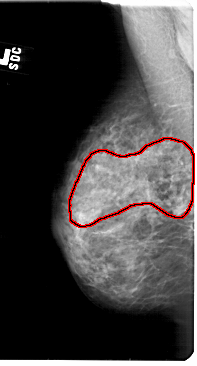

A_1851_1.LEFT_CC

LEFT_CC LINES 5236 PIXELS_PER_LINE 2836 BITS_PER_PIXEL 12 RESOLUTION 43.5 OVERLAY

FILE: A_1851_1.LEFT_CC.OVERLAY

TOTAL_ABNORMALITIES 1

ABNORMALITY 1

LESION_TYPE CALCIFICATION TYPE PLEOMORPHIC DISTRIBUTION SEGMENTAL

ASSESSMENT 4

SUBTLETY 3

PATHOLOGY MALIGNANT

TOTAL_OUTLINES 1

BOUNDARY